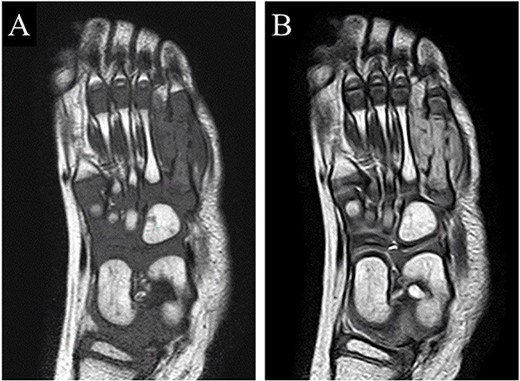

A 21-month-old Japanese female infant presented with a swollen mass on the dorsolateral aspect of the left foot. Her parents noticed the mass and brought the patient to our hospital. The patient had no past medical histories or complications prior to the occurrence. In addition, she received the BCG vaccine at the age of 4 months in Japan. At first visit to our hospital, physical examination revealed the ~3 × 3 cm mass was located on the dorsolateral aspect of the left foot and was hard accompanied by local heat (Fig. 1). Plain radiographs of the left foot showed a lytic lesion without periosteal reaction in the fifth metatarsal bone (Fig. 2). Magnetic resonance imaging (MRI) showed an isointense lesion on T1-weighted images and a hyperintense lesion on T2-weighted images around and within fifth metatarsal (Fig. 3). Gallium scintigraphy revealed intense uptake in the patient’s left foot (Fig. 4). In addition, laboratory examination was within normal. Based on medical history, clinical and imaging findings, we considered the possibility of neoplasia or osteomyelitis and performed an open debridement and biopsy of the lesion to make a diagnosis. The lesion was yellow and consisted of weak, adipose-like tissue that surrounded and continued into the inferior of the fifth metatarsal bone (Fig. 5). The lesion inside and outside the bone was resected as much as possible. Histopathologic examination of the lesion showed granulomatous inflammation including anaplastic giant cells, Langerhans-type giant cells and caseous necrosis (Fig. 6). Based on these results, TB or BCG osteomyelitis was considered as a diagnosis. The tuberculin test was positive, but the QuantiFERON TB test was negative. In addition, samples analyzed using polymerase chain reaction did not identify M. tuberculosis, but did identify the BCG Tokyo-172 strain. Per these findings, the patient was diagnosed with BCG osteomyelitis of the fifth metatarsal and oral treatment with anti-TB medicine including isoniazid (100 mg/day) and rifampicin (150 mg/day) was started. Clinical findings included reduction in swelling of the mass and gradual remodeling of the lytic lesion of the fifth metatarsal on plain radiographs (Fig. 7). However, 10 months after starting the anti-TB treatment, the mass recurred, and MRI revealed a residual high-intensity lesion around and inside the fifth metatarsal on T2-weighted fat-suppressed images (Fig. 8). It was determined that the lesion was difficult to control with anti-TB treatment alone, so an open debridement for the lesion was performed again. Histopathologic examination of the lesion revealed an epithelioid granuloma with necrosis. Therefore, the anti-TB treatment was continued. Six months after the second surgery, clinical and radiographic image findings showed complete improvement (Fig. 9). As a result, anti-TB treatment was ended. At the time of writing this report, 8 years after starting anti-TB treatment, there has been no recurrence.

MRI showed an isointense lesion on T1-weighted images and a hyperintense lesion on T2-weighted images around and within the fifth metatarsal.